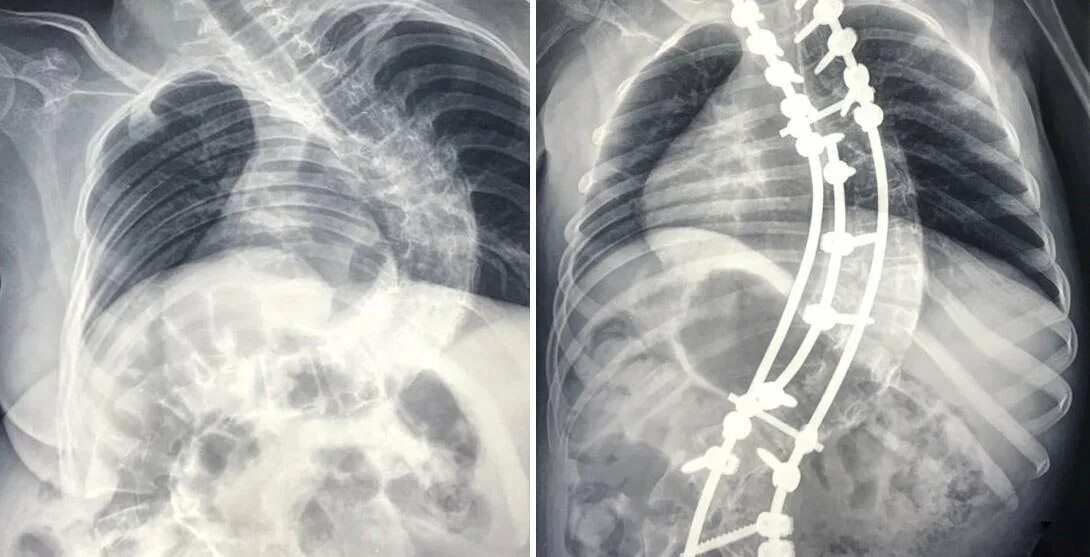

Сма справа